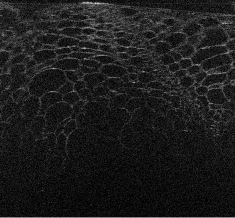

Visualizations of cross sectional reconstructions from the sub-sampled measurements are shown in Figure 2 and Figure 3 for the beaded gel and cucumber tissue samples respectively. Quantitative results of the NCC are then shown in Table 1.

The cucumber tissues results in Figure 3 follow a similar trend to the beaded phantom, with very good preservation of structure for random and equispaced sub-sampling for both MBIR techniques. Again, partial measurements are significantly worse, with most of the structure degraded in the interpolated ISAM image.